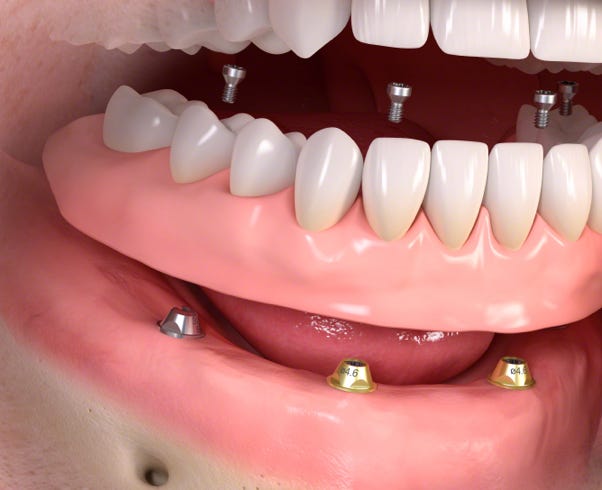

Mit implantologischen Fragestellungen sind Sie in unserer Praxis bestens aufgehoben.

Unsere Praxis ist seit über 10 Jahren implantologisch zertifiziert und verfügt über den anerkannten „Tätigkeitsschwerpunkt Implantologie“.

Was ist ein Dentalimplantat überhaupt ?

Eine künstliche Wurzel, die wie eine natürliche funktioniert.

Wenn ein Zahn und seine Wurzel fehlen, ist die langfristige Lösung für eine natürliche Funktion ein Dentalimplantat mit dazu passender Krone.

Über Zahnimplantate

Ein Dentalimplantat ist ein kleiner, aber stabiler Pfosten aus biokompatiblen Metallen oder Keramiken. Es wird unter Lokalanästhesie anstelle der fehlenden Zahnwurzel in den Kieferknochen gesetzt und fungiert als Stütze für den Zahn.

Die Einheilphase dauert zwischen 6 und 12 Wochen, abhängig von der individuellen medizinischen Situation. Während dieses Zeitraums wird das Implantat sicher im Kieferknochen befestigt – ein als Osseointegration bezeichneter Prozess. Nach der Einheilung fungiert diese künstliche Wurzel als Basis für die Befestigung einzelner Kronen, mehrgliedriger Brücken oder einer Totalprothese.